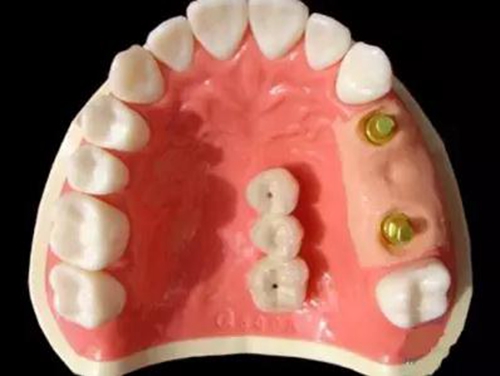

種植支持式固定義齒外展隙面積影響食物嵌塞

8月13日在線發(fā)表于《牙周病學(xué)雜志》(J Periodont)的一項(xiàng)橫斷面研究顯示,種植支持式固定義齒和鄰牙間的食物嵌塞更易發(fā)生于鄰接觸喪失及外展隙表面積(ESA)增加的情況下。食物嵌塞降低了患者的總體滿意度。外展隙尺寸影響牙周/種植體周黏膜的狀態(tài)及種植體的骨水平。

本研究納入了100例患者(55 例男性,45 例女性),平均年齡56歲(27~83歲),共150個(gè)固定義齒的215個(gè)外展隙。牙周/種植體周圍黏膜狀態(tài)、外展隙尺寸及患者總體滿意度作為解釋變量。

結(jié)果在種植支持式固定義齒和鄰牙間的215個(gè)外展隙中,96個(gè)(44.7%)有食物嵌塞。鄰接觸喪失外展隙較緊密接觸者更易發(fā)生食物嵌塞(P=0.009)。鄰面外展隙的食物嵌塞降低了總體滿意度(P=0.012)。在外展隙參數(shù)中,僅ESA明顯影響食物嵌塞(P=0.034)。不同的外展隙尺寸對(duì)牙周/種植體周黏膜狀態(tài)和種植體骨水平有顯著影響。

5.jpg